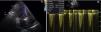

Mulher de 78 anos, com fibrilhação auricular paroxística e portadora de prótese aórtica mecânica desde há dez anos, sob hipocoagulação oral. Internamento recente por dor torácica associada a supradesnivelamento de ST anterior. Dos exames realça‐se: coronariografia sem doença coronária epicárdica, evidenciando imagem compatível com trombo na artéria descendente anterior distal; aortografia objetivou regurgitação aórtica moderada; ecocardiograma revelou gradientes transprotésicos elevados sugestivos de mismatch/hiperfluxo e regurgitação ligeira (Figura 1). Quadro interpretado como enfarte embólico; alta com indicação de controlo rigoroso de INR e agendamento de ecocardiograma transesofágico para avaliação protésica.

Ecocardiograma transtorácico: A) prótese mecânica aórtica (Medtronic 21®) com insuficiência aórtica de grau ligeiro, possivelmente periprotésica; B) gradientes transprotésicos elevados (máximo 51mmHg e médio 24mmHg); tempo de aceleração 89ms; VTICSVE/VTIAo 0,29; área indexada 0,83cm2/m2, sugestivo de mismatch e/ou hiperfluxo.